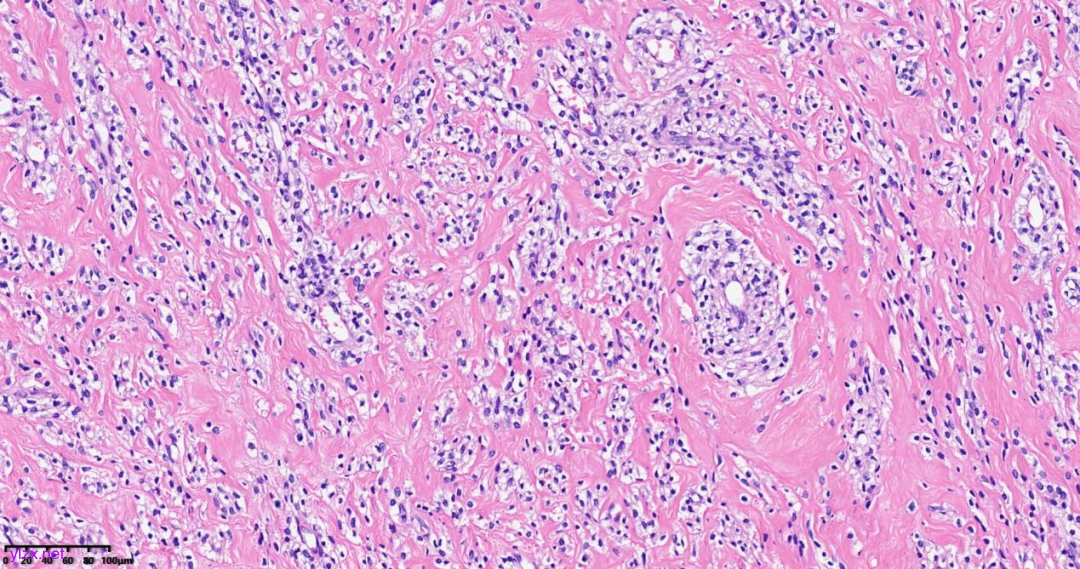

肿瘤细胞以梭形细胞、卵圆形细胞为主,部分为胞浆透亮的上皮样形态,透亮细胞界限较清,胞质淡染或胞浆丰富、嗜酸性,肿瘤内血管丰富,肿瘤细胞围绕血管周围片巢状、束状及放射状排列;肿瘤细胞核异型性不明显,核分裂像少见(<1个/50HPF),染色质开放,可见小核仁;肿瘤间质水肿、黏液变性,纤维胶原增生伴玻璃样变性。

图1~5 低倍镜下:肿瘤细胞以梭形细胞、卵圆形细胞为主,部分为胞浆透亮的上皮样形态,肿瘤细胞分布疏密不均,部分区密集丰富,部分区肿瘤细胞稀少,间质疏松水肿、黏液变性,肿瘤细胞围绕血管周围生长,局部间质纤维胶原增生伴玻璃样变性。

图6 中倍镜下:肿瘤内血管丰富,胞浆透亮的上皮样细胞围绕血管周围片巢状、束状及放射状排列。